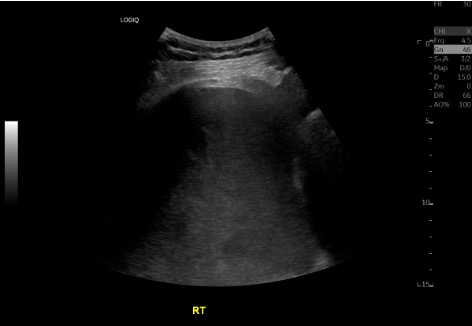

US survey — effusion + pre/post

Pre-procedure ultrasound showing right pleural effusion Pre-procedure CXR showing large left pleural effusion